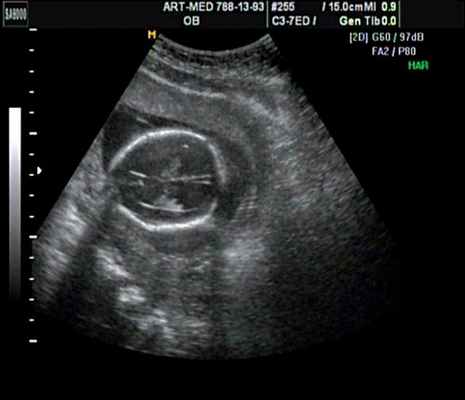

Клиническое наблюдение 4

Беременная 25 лет, обратилась в клинику в срок 18 нед. При эхографии выявлена грубая кифотическая деформация позвоночника в поясничном отделе (рис. 19).

В проекции деформации определяется миеломенингоцеле (рис. 20).

Обнаружение типичных эхографических признаков позволило установить диагноз миеломенингоцеле.